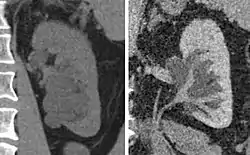

Peripelvic renal cysts may look like hydronephrosis on non-contrast CT (left image). However, CT urography (at right) reveals non-dilated calyces and pelvises.